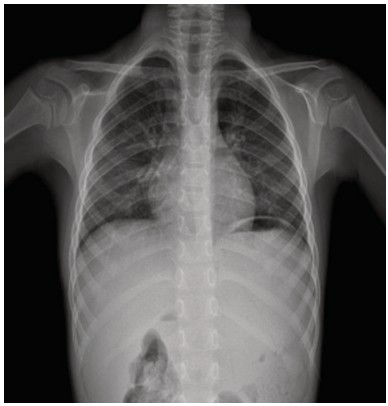

Figure 1. Chest X-ray at admission.

Chest X-ray (PA and lateral views) shows a centrally positioned trachea with normal patency. The cardiac silhouette is within normal limits. Pulmonary parenchyma displays adequate expansion. No consolidations or nodular lesions are present. There is an accentuation of bilateral interstitial and peribroncovascular markings. Both costophrenic and cardio phrenic angles are clearly visible. Soft tissues and bony structures appear unremarkable, with no visible abnormalities.

A 5-year-old boy with previous history of frequent admissions for pneumonia and acute asthma presented with 30 hours of nasal congestion and cough. His condition worsened over the last 6 hours, leading to respiratory distress and oxygen desaturation (measured by his mother as <80% at home). The patient's past medical history includes allergic rhinitis and asthma, managed with fluticasone and fexofenadine. There is a history of four previous hospitalizations for acute asthma and pneumonia, the most recent occurring two months ago and treated with antibiotics. His immunization status is incomplete for his age. The parents deny any exposure to tobacco smoke or biomass fuels. On physical examination, his oxygen saturation was 77%, respiratory rate 43/min, and heart rate 129/min. He appeared pale, with perioral cyanosis. The conjunctival, nasal and oropharyngeal mucosa showed erythema. Intercostal retractions were noted along with diminished breath sounds with no wheezing and a peculiar finding of bilateral high-pitched rales. There were no other clinical findings of relevance. Oxygen and inhaled salbutamol (albuterol) were started. Laboratory investigations, including a complete blood count, venous blood gas analysis, C-reactive protein, and a respiratory micro-array PCR panel, were unremarkable, except for a mild elevation in the absolute number of lymphocytes (Table 1). The chest X-ray revealed accentuated bilateral interstitial and peribroncovascular markings (Figure 1).